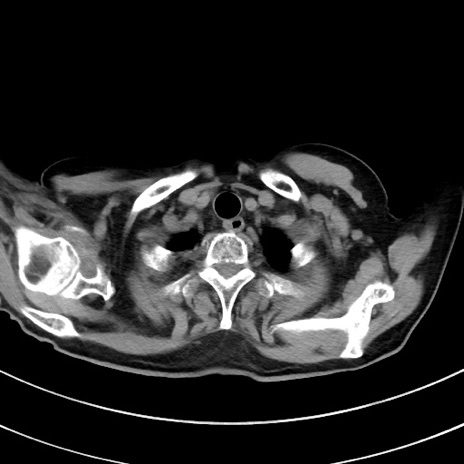

症例33(横断像)

【症例】70歳代 女性

【主訴】心窩部痛

【現病歴】延髄病変の精査・加療にて神経内科入院中。本日より心窩部痛あり。

【身体所見】右下腹部を中心に圧痛と反跳痛あり。

【データ】WBC 10900、CRP 0.02